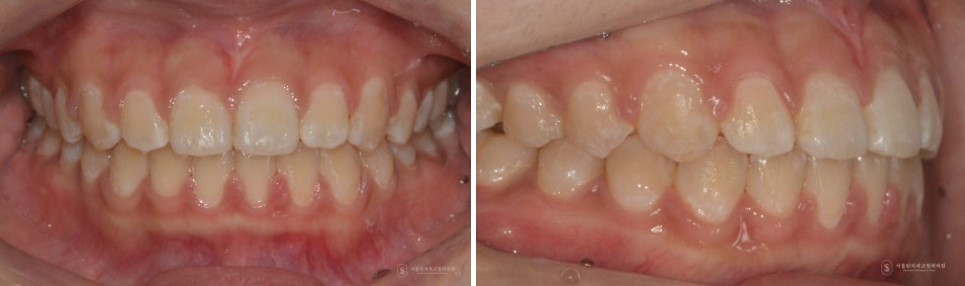

이후 교정적으로 위 앞니 사이의 공간을 닫아 정중이개를 해소하고, 마지막으로 재발 방지를 위한 상순소대 절제술을 시행했습니다.

그 결과, 단순히 앞니 사이 공간만 닫힌 것이 아니라 정중이개, 교합, 위아래 앞니 크기 밸런스까지 함께 개선되는 치료 결과를 얻을 수 있었습니다.